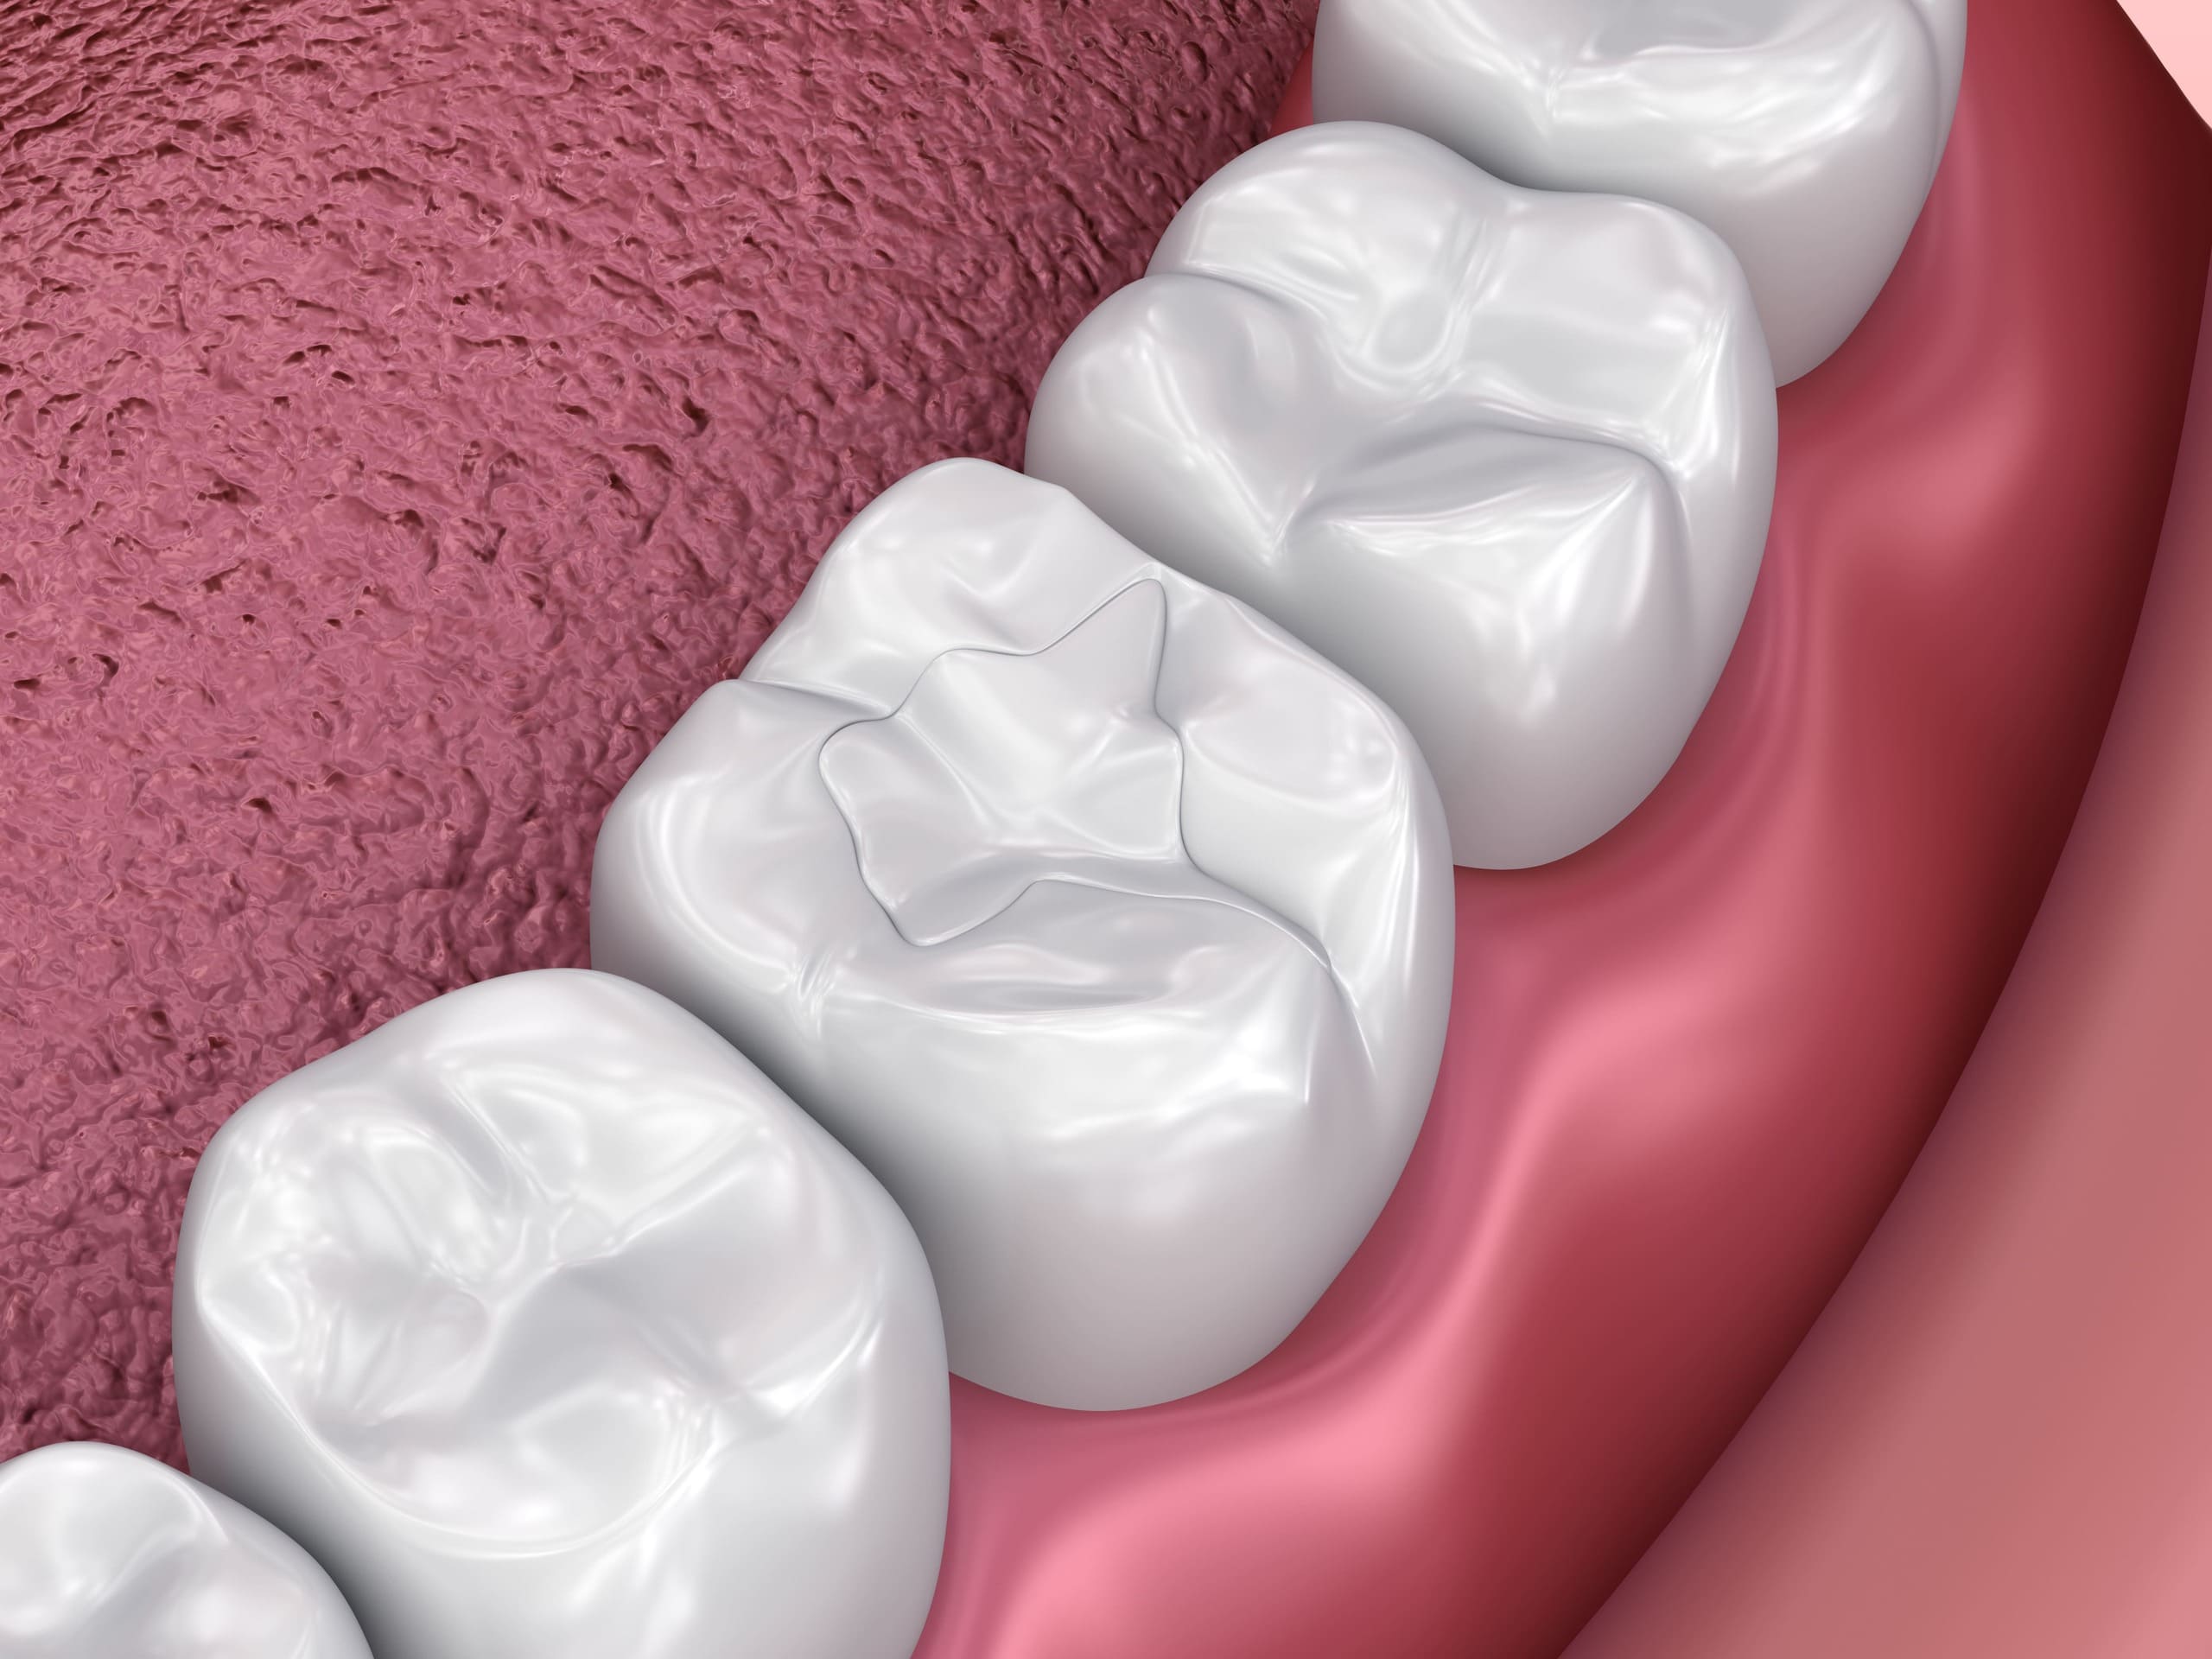

5 Benefits of Tooth-Colored Fillings